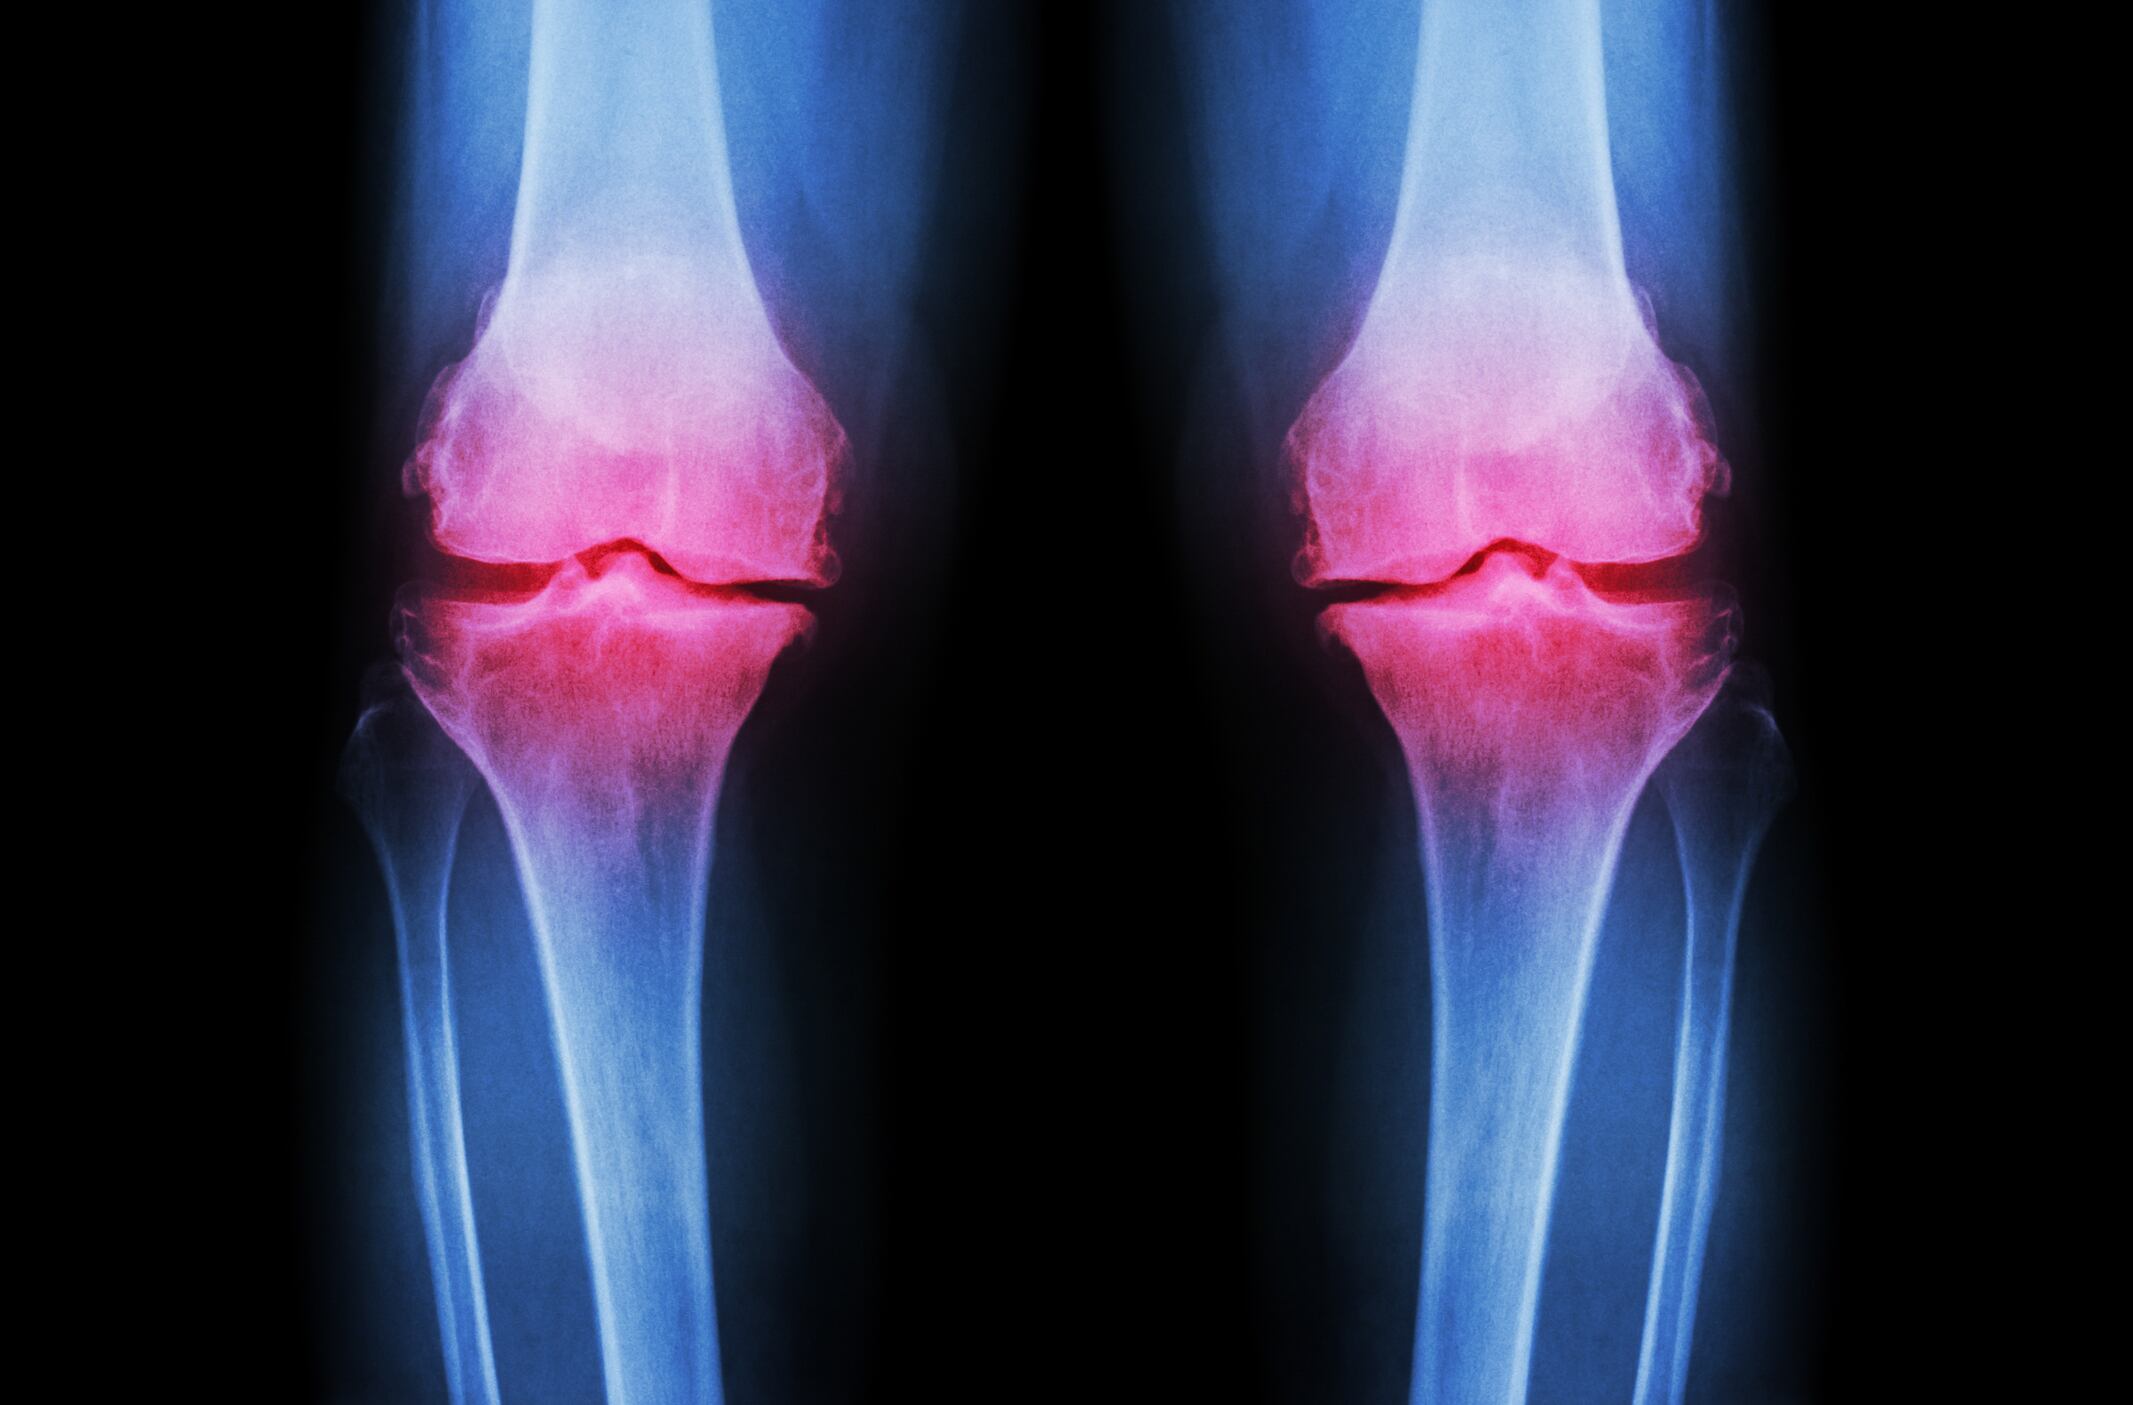

The water-soluble chicken eggshell membrane ingredient BiovaFlex may help support joint health and function, says a new study.